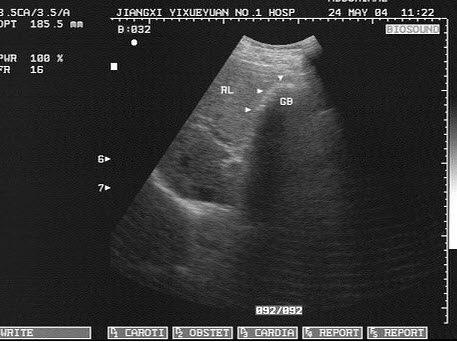

10、单项选择题

女,40岁,有时右上腹隐痛2年余。结合超声声像图,最可能的诊断为()